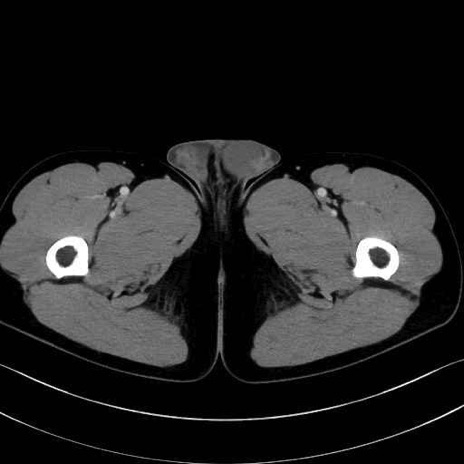

外閉鎖筋 (Obturator externus)